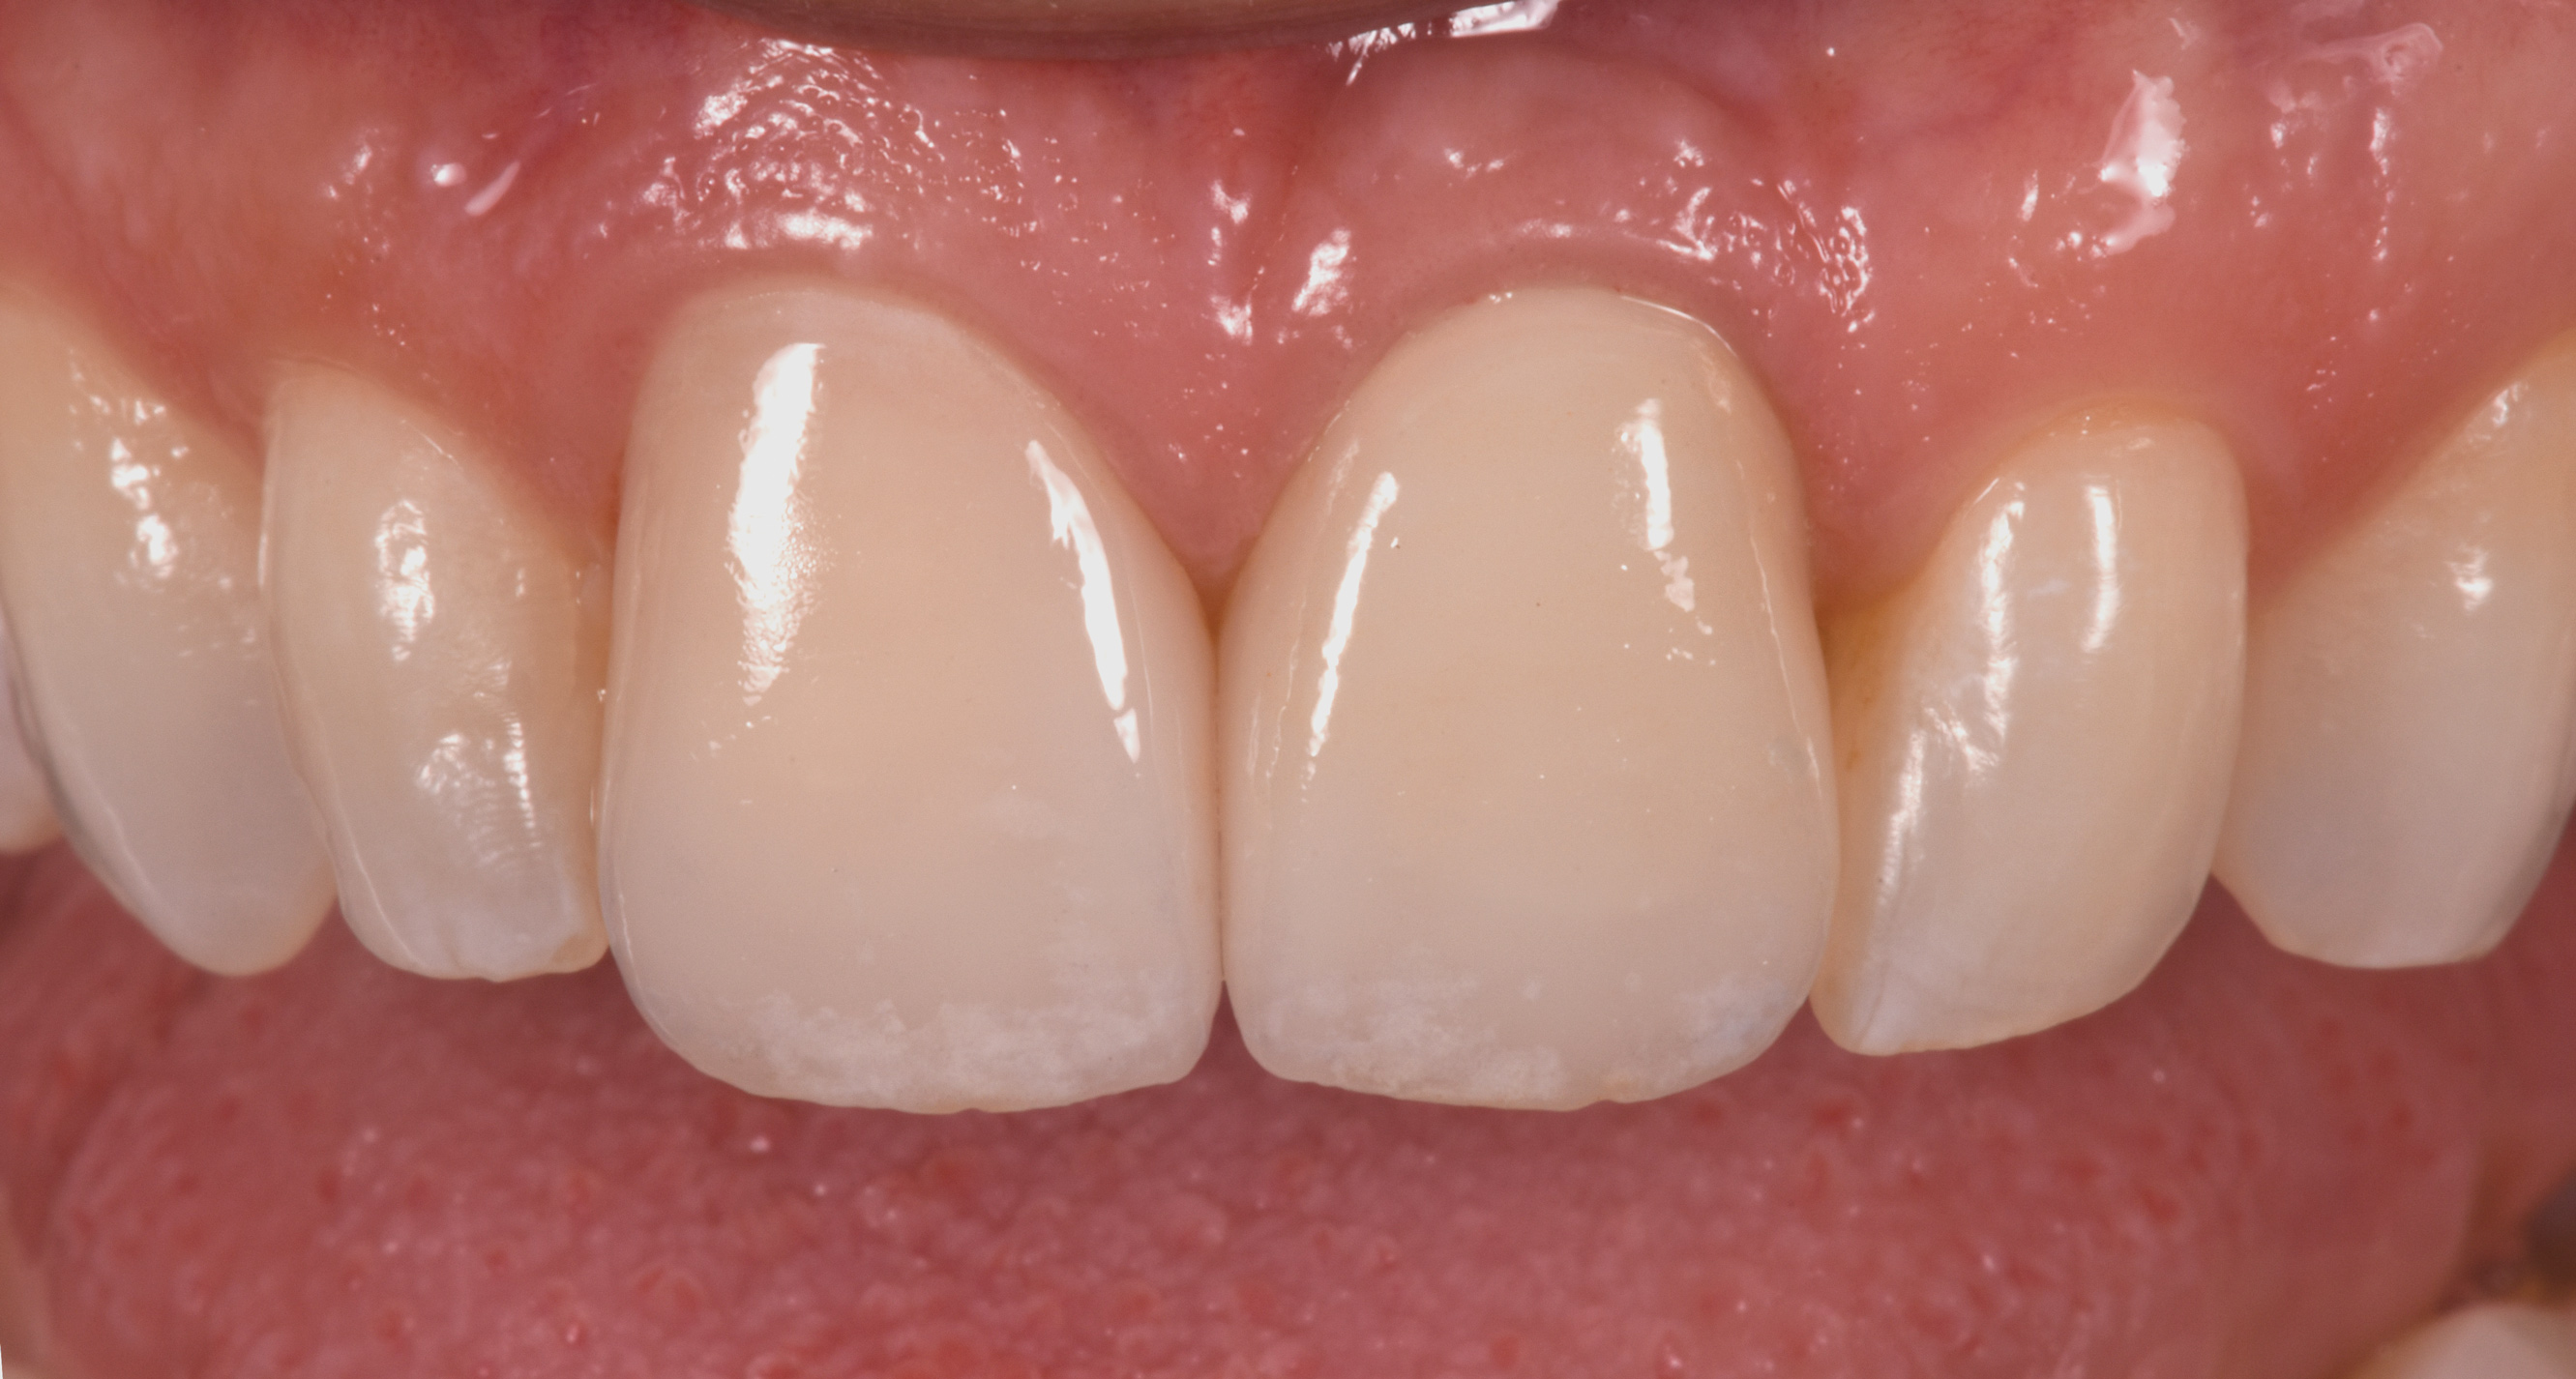

Fig 10. Labial view (laboratory [Fig 10] and clinical [Fig 11]) of crown Nos. 8 and 9 (implant-retained crown using angulated screw channel).

Fig 10 and Fig 11. Labial view (laboratory [Fig 10] and clinical [Fig 11]) of crown Nos. 8 and 9 (implant-retained crown using angulated screw channel).

Figure 11